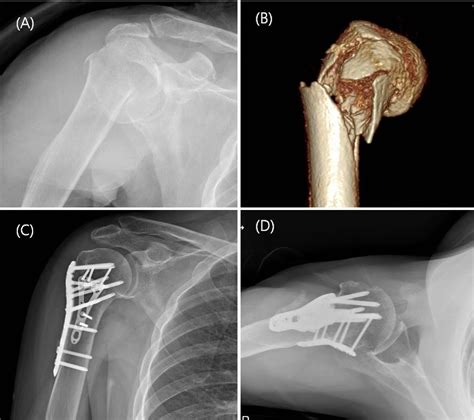

dual plate technique

dual plate technique. There are any references about dual plate technique in here. you can look below.